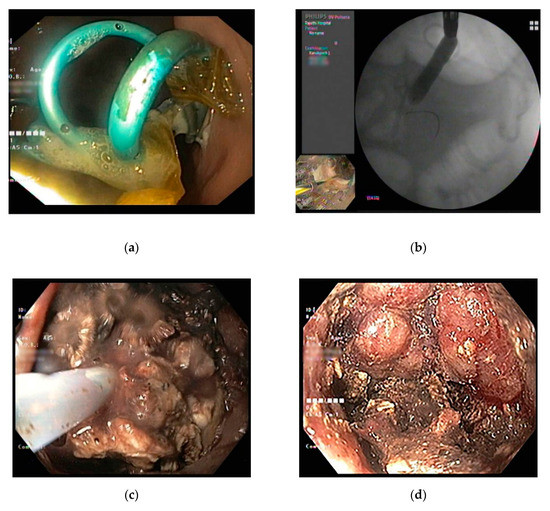

4. Endoscopic Drainage

4.1. SEMS as an Adjunctive Strategy to Improve Endoscopic Drainage

4.2. Endoscopic Necrosectomy

4.2.1. Technical Aspects of Endoscopic Necrosectomy